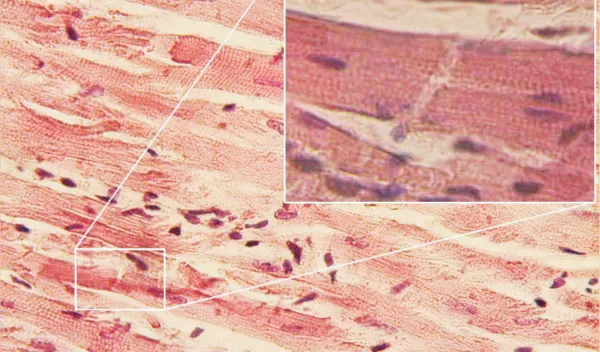

The researchers discovered this functionality in human tissue using a heart-on-a-chip with embedded sensors that continuously tracked the contractions of the tissue.

The scientists found that in tissues treated with EEVs, heart cells could better adapt to stress conditions and sustain a higher workload. Heart tissue treated with EEVs had half as many dead cells and had a contractile force four times higher than untreated tissue.